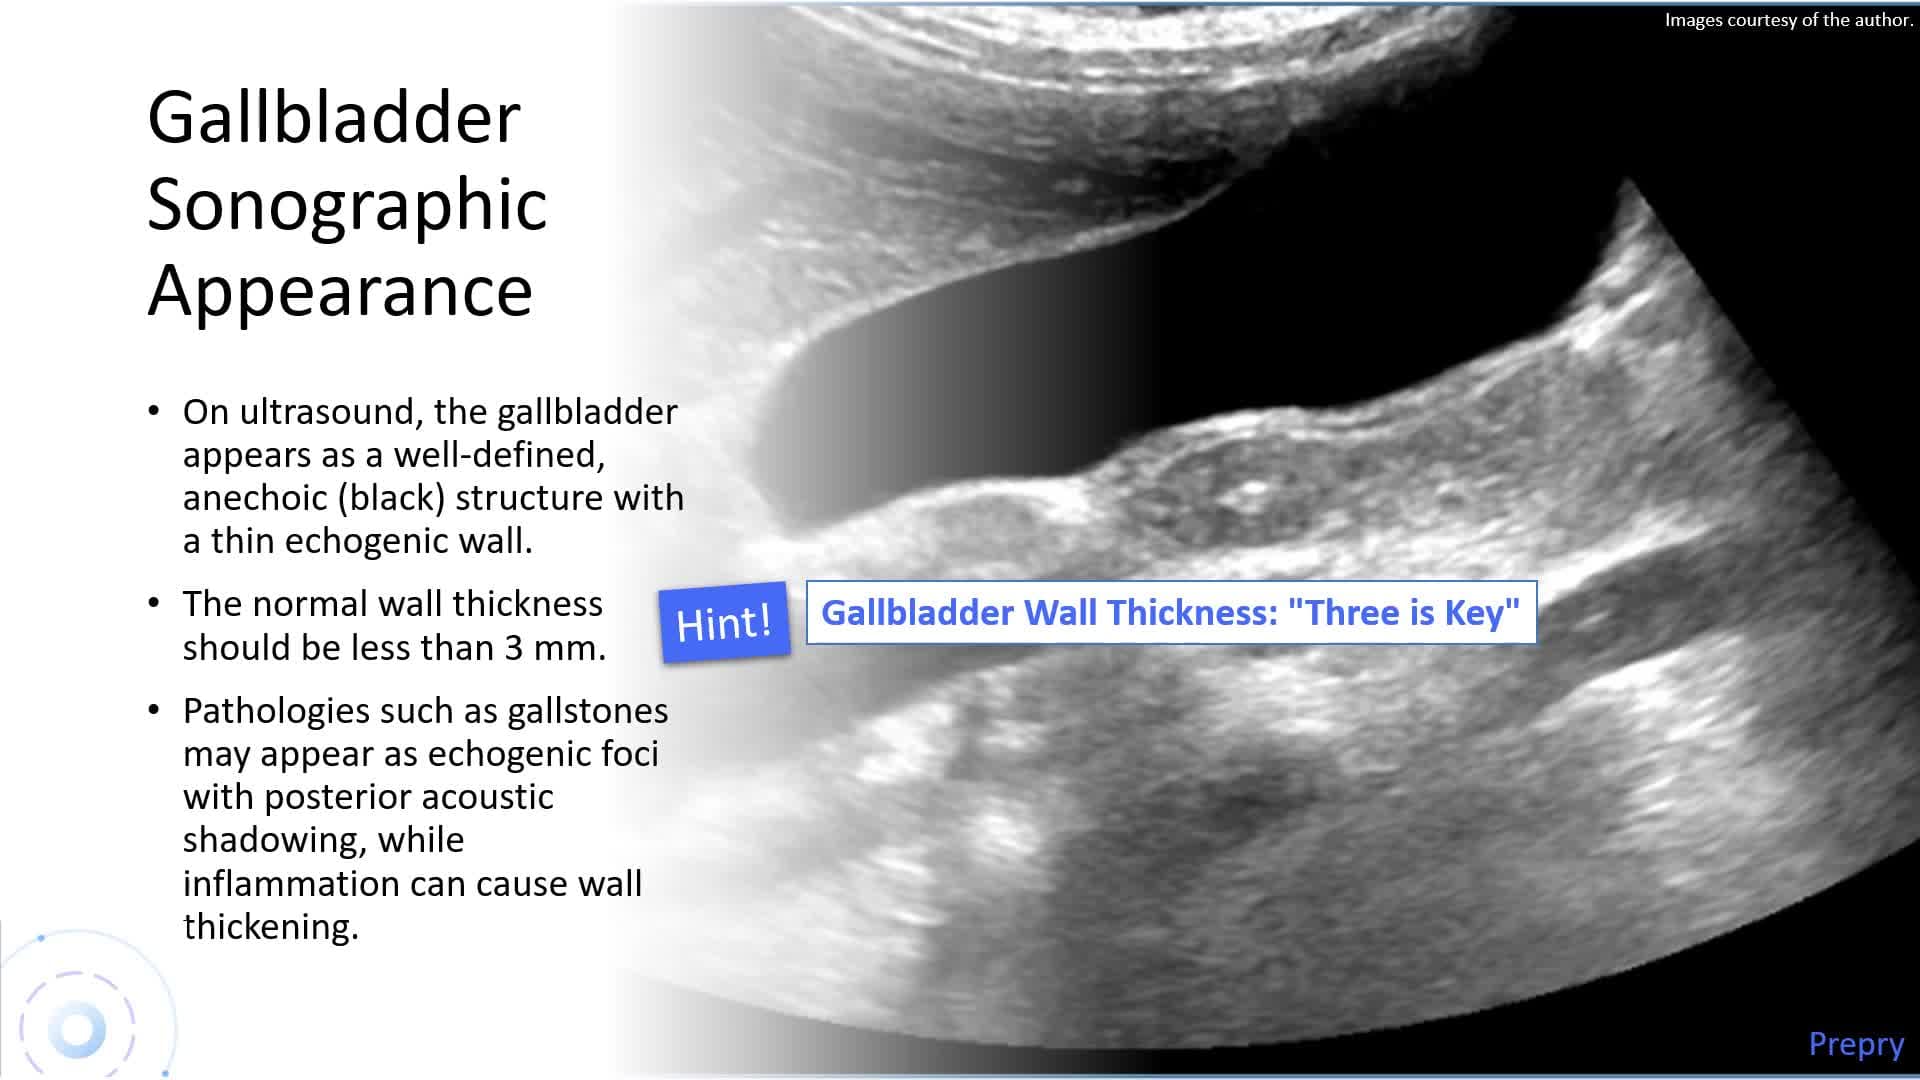

Biliary System and Pancreas - Part 1: Biliary System

Biliary System